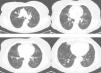

Observación clínicaMujer de 73 años sin antecedentes de interés. Una radiografía de tórax preoperatoria objetivó varios nódulos pulmonares. La paciente se encontraba asintomática. El hemograma y las determinaciones bioquímicas en suero y orina resultaron normales. La TAC torácica mostró múltiples nódulos pulmonares bilaterales de tamaño variable, entre 1 y 10mm, y 2 de mayor tamaño, uno de 20mm en el lóbulo superior derecho y otro de 12mm en el lóbulo inferior derecho (fig. 1). Las pruebas de función respiratoria resultaron normales. Un estudio para buscar un proceso neoplásico primario, que incluyó TAC abdominopélvica, valoración ginecológica y PET-TAC, resultó negativo. Endoscópicamente el árbol bronquial no presentó alteraciones significativas y los estudios citológicos y microbiológicos de las muestras broncoscópicas (aspirado y cepillado bronquiales, y lavado broncoalveolar) resultaron negativos. Se realizó una punción-aspiración del nódulo de mayor tamaño que mostró un tumor fusocelular de bajo grado nuclear e inmunofenotipo neuroendocrino (panqueratinas, cromogranina y CD56 positivos, y vimentina y S-100 negativos; fig. 2). Dada la multifocalidad de las lesiones se planteó el diagnóstico diferencial con metástasis de una neoplasia mesenquimal, melanoma o carcinosarcoma. Se realizó una biopsia por videotoracoscopia, que mostró 2 tumorlets carcinoides de 4 y 3mm de diámetro. Su estudio inmunohistoquímico reveló positividad para CD-56 y TTF-1, y el índice de proliferación celular (Ki67) resultó inferior al 2%. Por la multiplicidad del proceso se descartó un tratamiento quirúrgico, y el tratamiento quimioterápico tampoco se consideró adecuado teniendo en cuenta el índice de proliferación, por lo que se decidió una pauta de observación. A los 24meses se mantenía asintomática, con una función pulmonar normal, y los nódulos se mantenían en su mayoría estables, habiendo crecido mínimamente 2 de los de mayor tamaño (3 y 4mm).